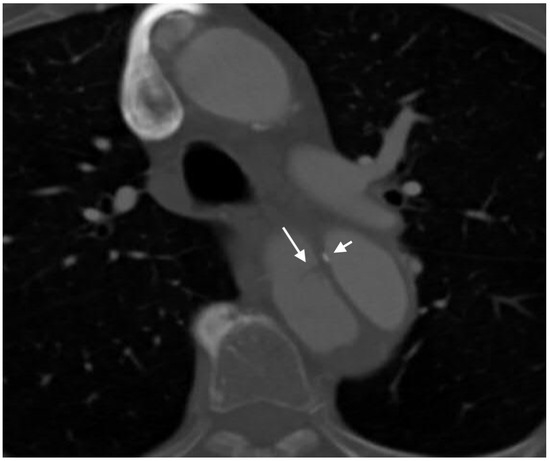

2.4.3. Arterial Dissection